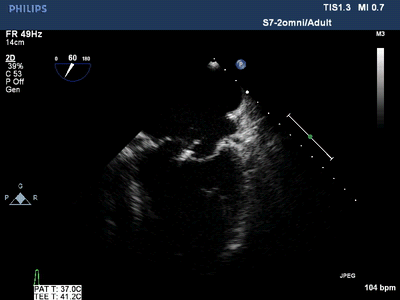

潍坊市第二人民医院超声医学科自2019年开展经食管超声心动图检

市中心医院超声医学科成功完成经食管超声心动图检查 据了解,经食管

而"经食管超声心动图监测技"将超声探头经口腔放置于食道和胃底,能够